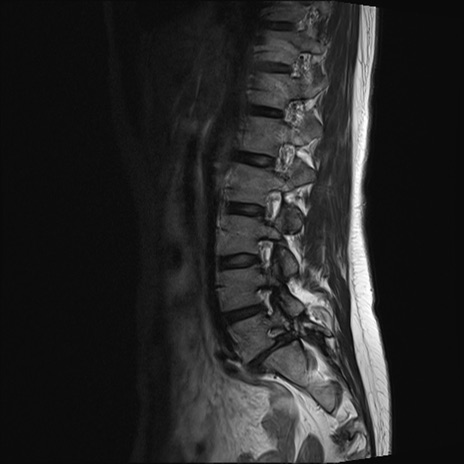

【整形】TIPS症例4 腰椎MRI T2WI(矢状断像)

腰椎MRI

T1WI(矢状断像)